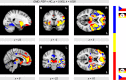

To identify progressive supranuclear palsy (PSP), we combined voxel-based morphometry (VBM) and support vector machine (SVM) classification using disease-specific features in multicentric magnetic resonance imaging (MRI) data. Structural brain differences were investigated at four centers between 20 patients with PSP and 20 age-matched healthy controls with T1-weighted MRI at 3T. To pave the way for future application in personalized medicine, we applied SVM classification to identify PSP on an individual level besides group analyses based on VBM. We found a major decline in gray matter density in the brainstem, insula, and striatum, and also in frontomedian regions, which is in line with current literature. Moreover, SVM classification yielded high accuracy rates above 80% for disease identification in imaging data. Focusing analyses on disease-specific regions-of-interest (ROI) led to higher accuracy rates compared to a whole-brain approach. Using a polynomial kernel (instead of a linear kernel) led to an increased sensitivity and a higher specificity of disease detection. Our study supports the application of MRI for individual diagnosis of PSP, if combined with SVM approaches. We demonstrate that SVM classification provides high accuracy rates in multicentric data-a prerequisite for potential application in diagnostic routine.